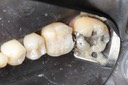

Matt Dodson #3 prep